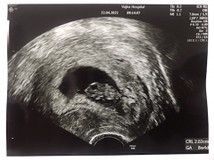

ซาวน์ทางช่องคลอดค่ะ ตอน 8 วีค 4 วันค่ะ เห็นหัวใจเต้นในจอ จริงๆซาวน์ครั้งแรกตอน 6 วีค 4 วันเจอตัวหัวใจเต้นกะพริบแล้วค่ะ